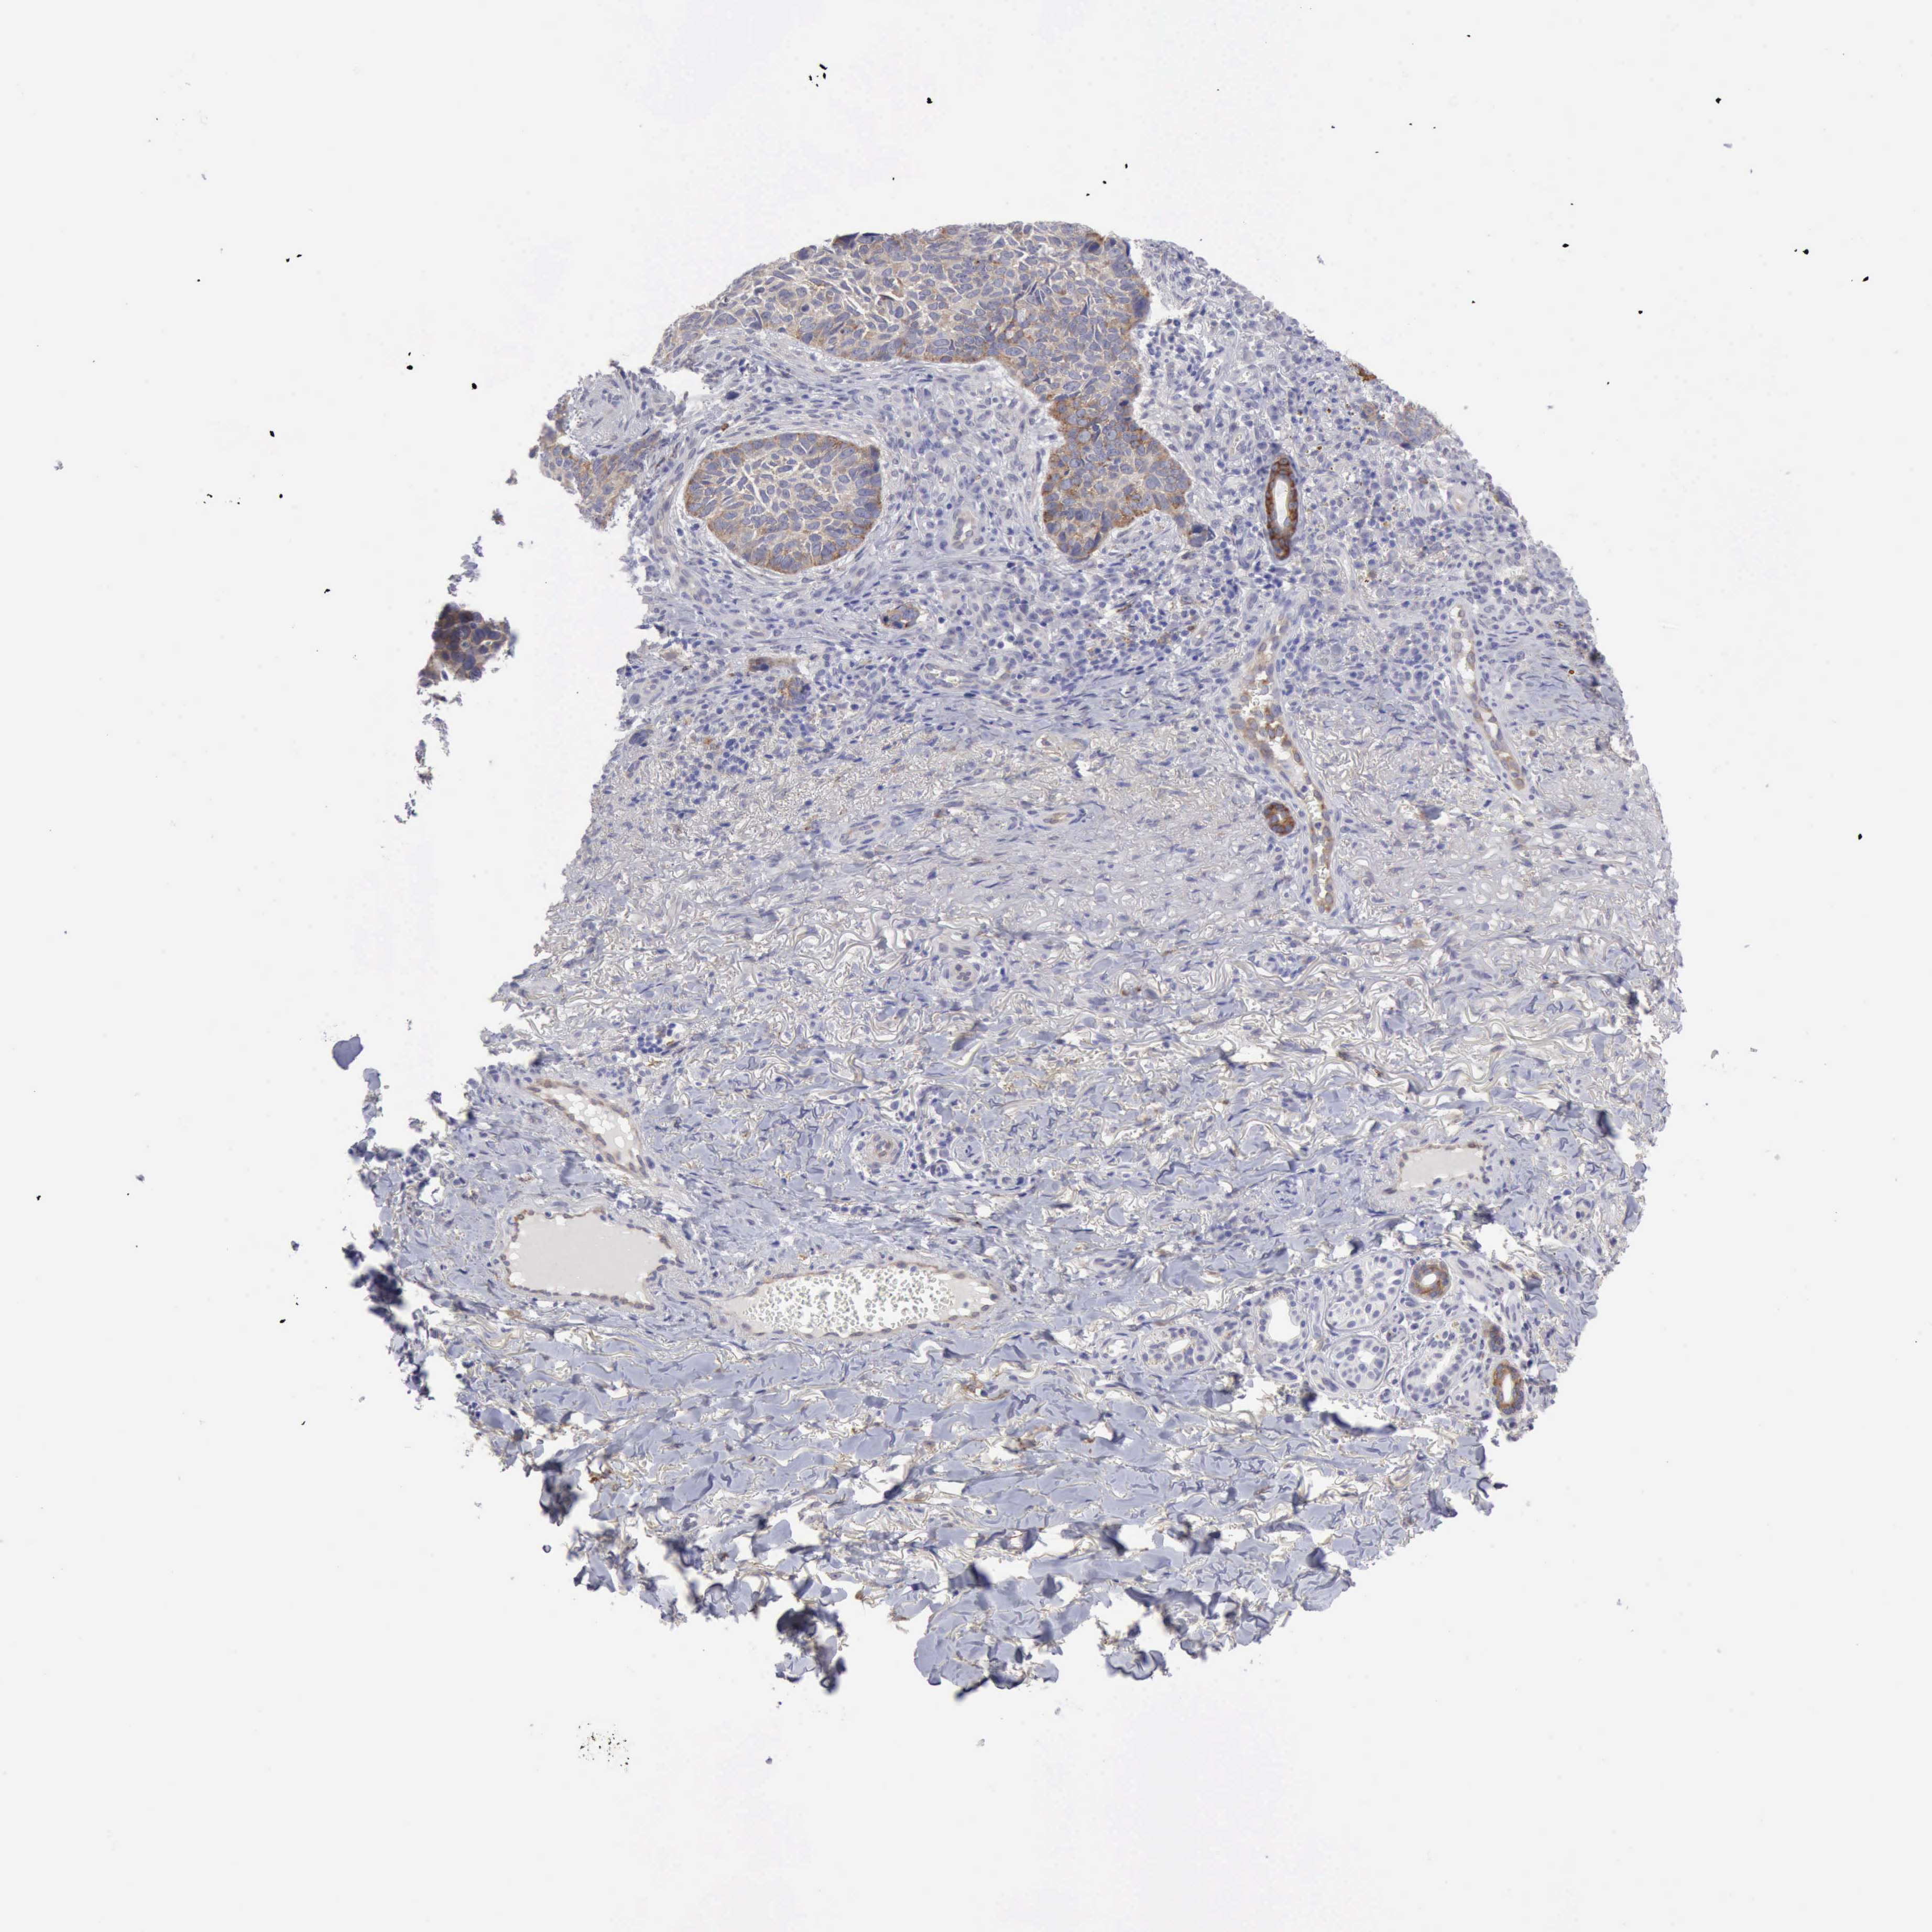

SKIN CANCER - Protein expressioni

A mouse-over function shows sample information and annotation data. Click on an image to view it in a full screen mode. Samples can be filtered based on level of antibody staining by selecting one or several of the following categories: high, medium, low and not detected. The assay and annotation is described here.

Each image is clickable and will lead to virtual microscopy that enables deeper exploration of all samples and also displays staining intensity scores, fraction scores and subcellular localization as well as patient and tissue information for each sample.

Antibody CAB000153

Squamous cell carcinoma, NOS